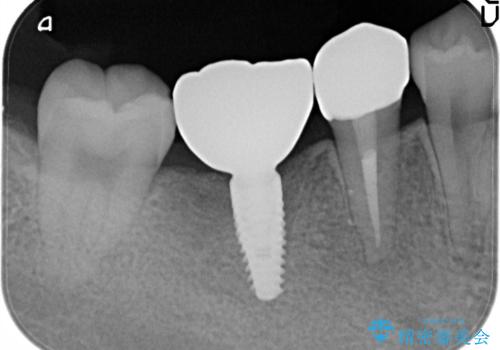

- 右下の奥歯の調子がよくないとのことで来院されました。

レントゲン・口腔内診査をお行い、保存が難しいことがわかりました。

抜歯後インプラントをする計画としました。

見た目では問題がなさそうでも、レントゲン撮影・診査を行うと状態が悪くなっていることがあります。